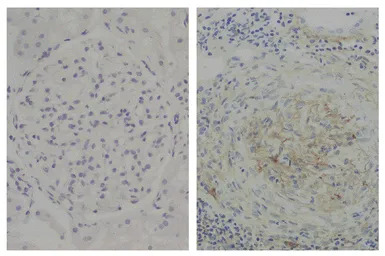

IHC-P analysis of human glomerular basement membrane tissue using GTX04181 Mouse Anti-Human IgG2 (Fd) antibody [HP6014] followed by an HRP conjugated secondary antibody.